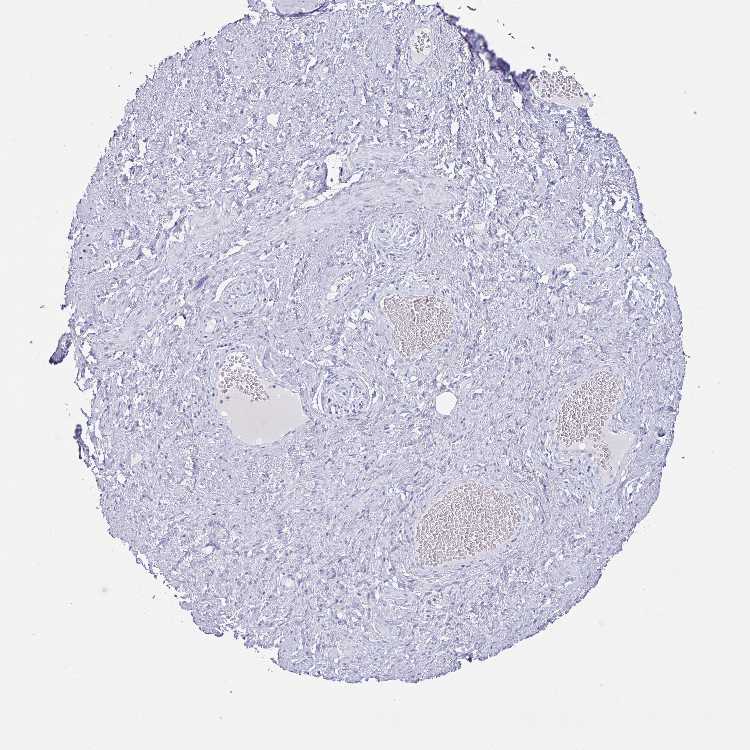

SOFT TISSUE 2 - Antibody stainingi

Antibody staining in the annotated cell types in the current human tissue is reported as not detected, low, medium, or high, based on conventional immunohistochemistry profiling in selected tissues. This score is based on the combination of the staining intensity and fraction of stained cells.

Each image is clickable and will lead to virtual microscopy that enables deeper exploration of all samples and also displays staining intensity scores, fraction scores and subcellular localization as well as patient and tissue information for each sample.

Antibody HPA058909

Fibroblasts Not detected

Peripheral nerve Not detected